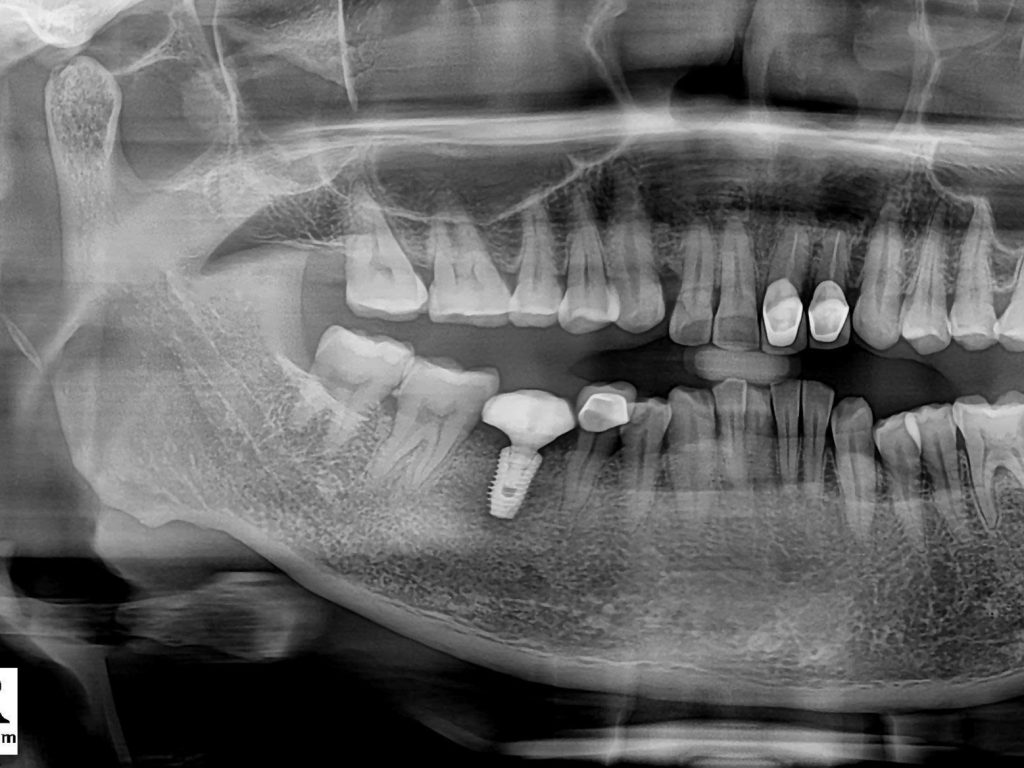

Hệ Thống Chẩn Đoán CT Conebeam 3D

X-Quang 3D giúp lập kế hoạch giả định cá nhân hóa, tối ưu hóa độ chính xác và kiểm soát rủi ro phẫu thuật.

Bước 1 – Thăm Khám & Chụp XQ 3D